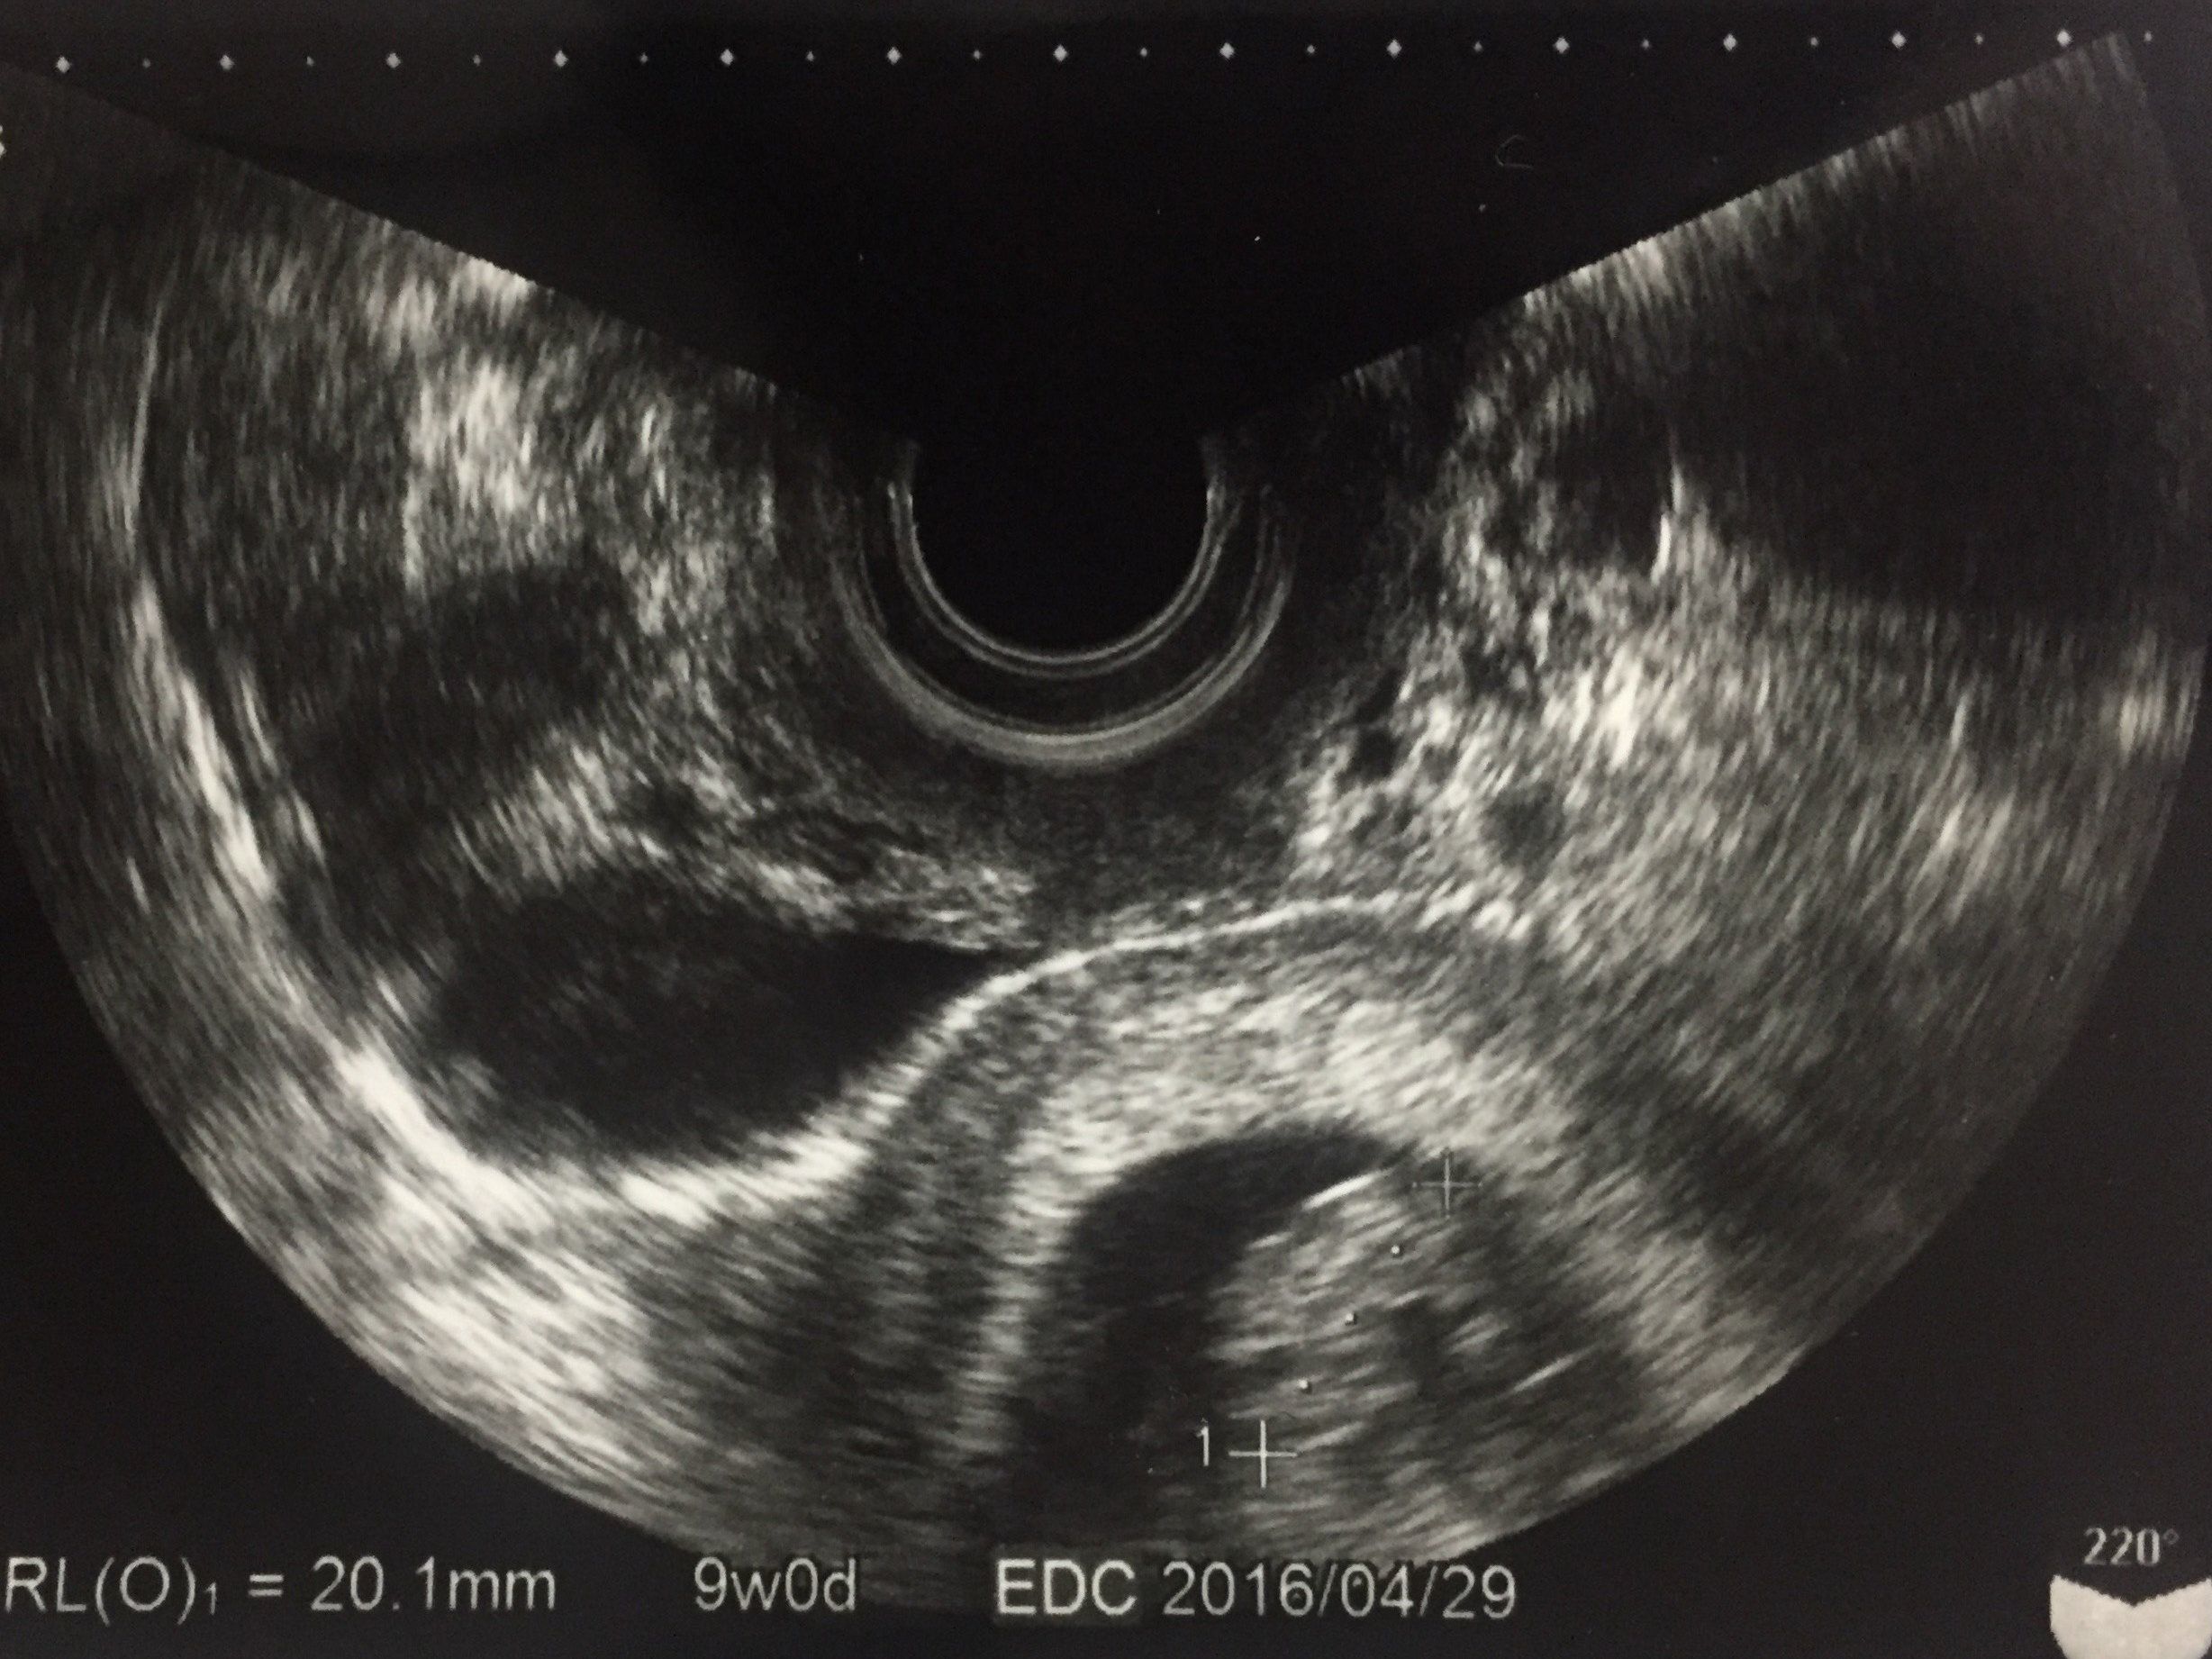

妊娠9週目 心拍を確認! つわりのピーク

無事に挙式が終わり、2回目の健診で心拍が確認できて安心しました。母子手帳も交付され、妊婦なのだと実感が湧きました。

この頃は毎朝気分が悪く、何か食べるとおさまる「食べづわり」でした。日中も気分が悪くなることがありましたが、仕事は続けていました。

勤務先に報告するのはまだ早いだろうと思いつつ、体調が悪くなったらどう説明しようかと悩んでいた時期です。